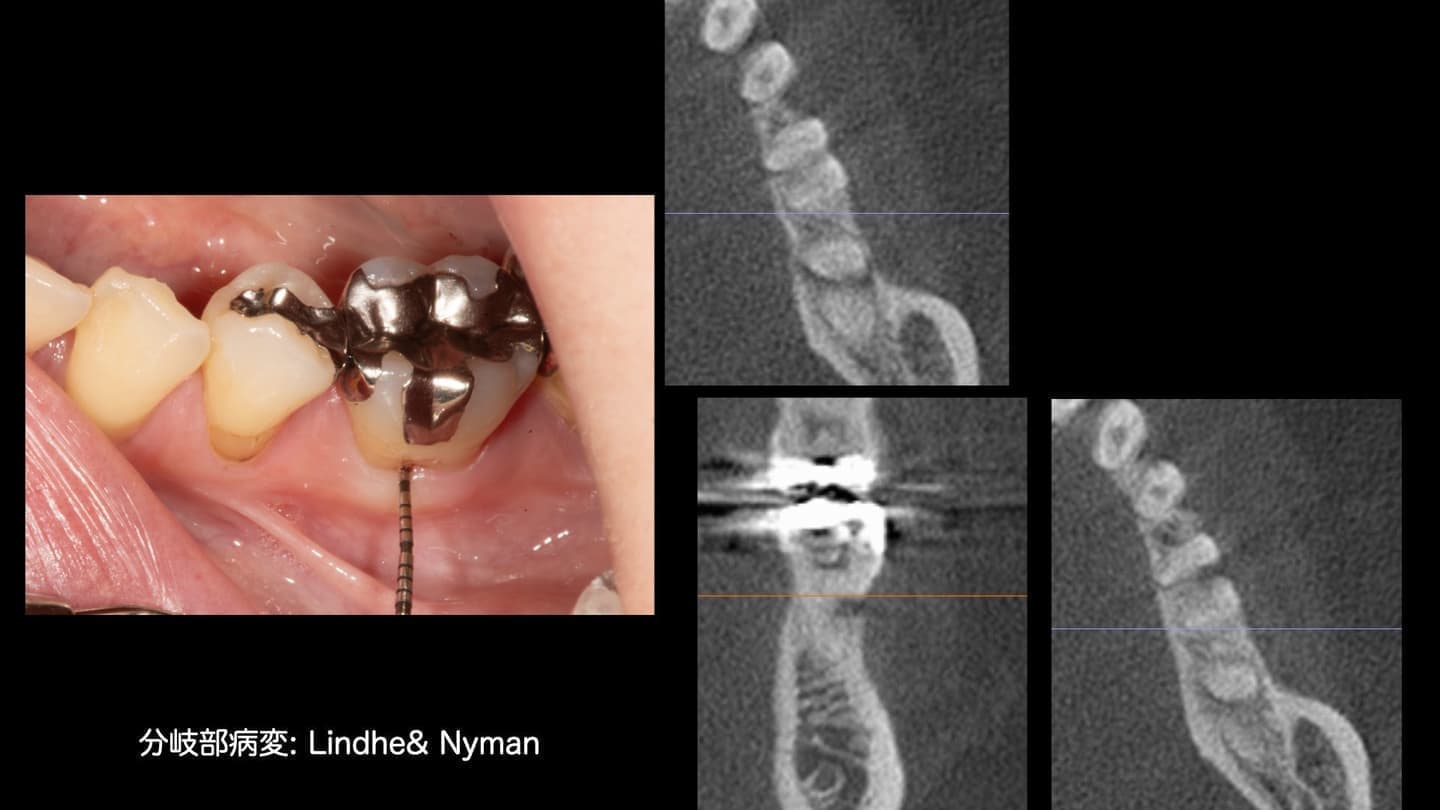

あらゆる検査からの情報を分析します

基本的な検査だけでなく、CT検査、歯周病に特異的な細菌のPCR検査、噛み合わせの検査、生活習慣の見直しなどを行います